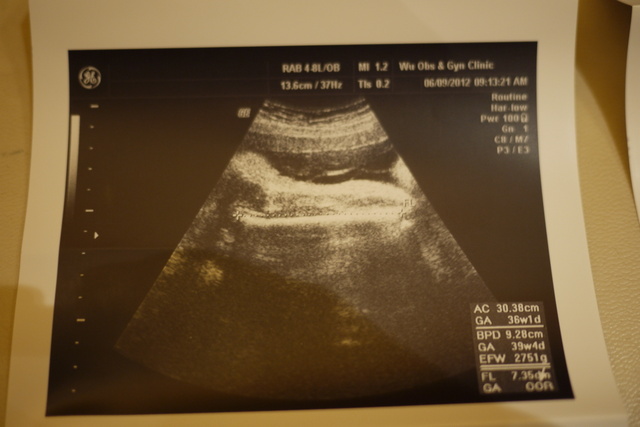

第37 (第十月 )

感已大到面都快放不下~~~~~肉好多唷~~~~~

小果的一直都是朝下的!!!!!而且非常下面!!!!!!胎位偏低.....

第38 (第十月 )

是部的特.....

外面那圈白白的就是骨......

第39 (第十月 )

是大腿骨的特.......

次也是最後一次......